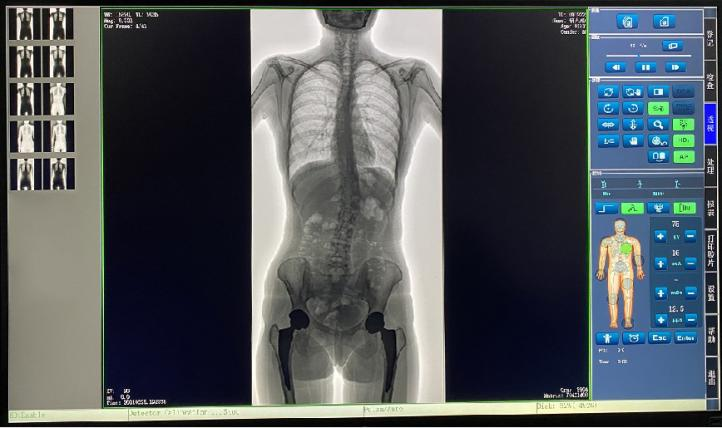

普愛醫(yī)療新推出一款動態(tài)平板DR-PLX8600,這款產品可攝影、可透視、可造影,臨床適用范圍廣泛,可滿足不同臨床拍攝需求。一體式的機架,擺位簡單快捷,不僅融合了市面上17英寸動態(tài)DR的所有功能,還有獨具特色的超大動態(tài)視野范圍,給臨床應用帶來醫(yī)療診斷價值,降低醫(yī)院設備投入成本,獲得更大收益。

1.專為大視野臨床應用打造的平板動態(tài)DR,圖像不拼接,有效簡化影像科室檢查流程,提高診斷精度,降低患者吸收的輻射劑量。

2.解決了拼接圖像存在密度不均勻,拼接處圖像配準和放大效應等問題,輻射劑量小。

7.自研軟件系統(tǒng),功能區(qū)劃分合理,操作便捷,圖像處理清晰。